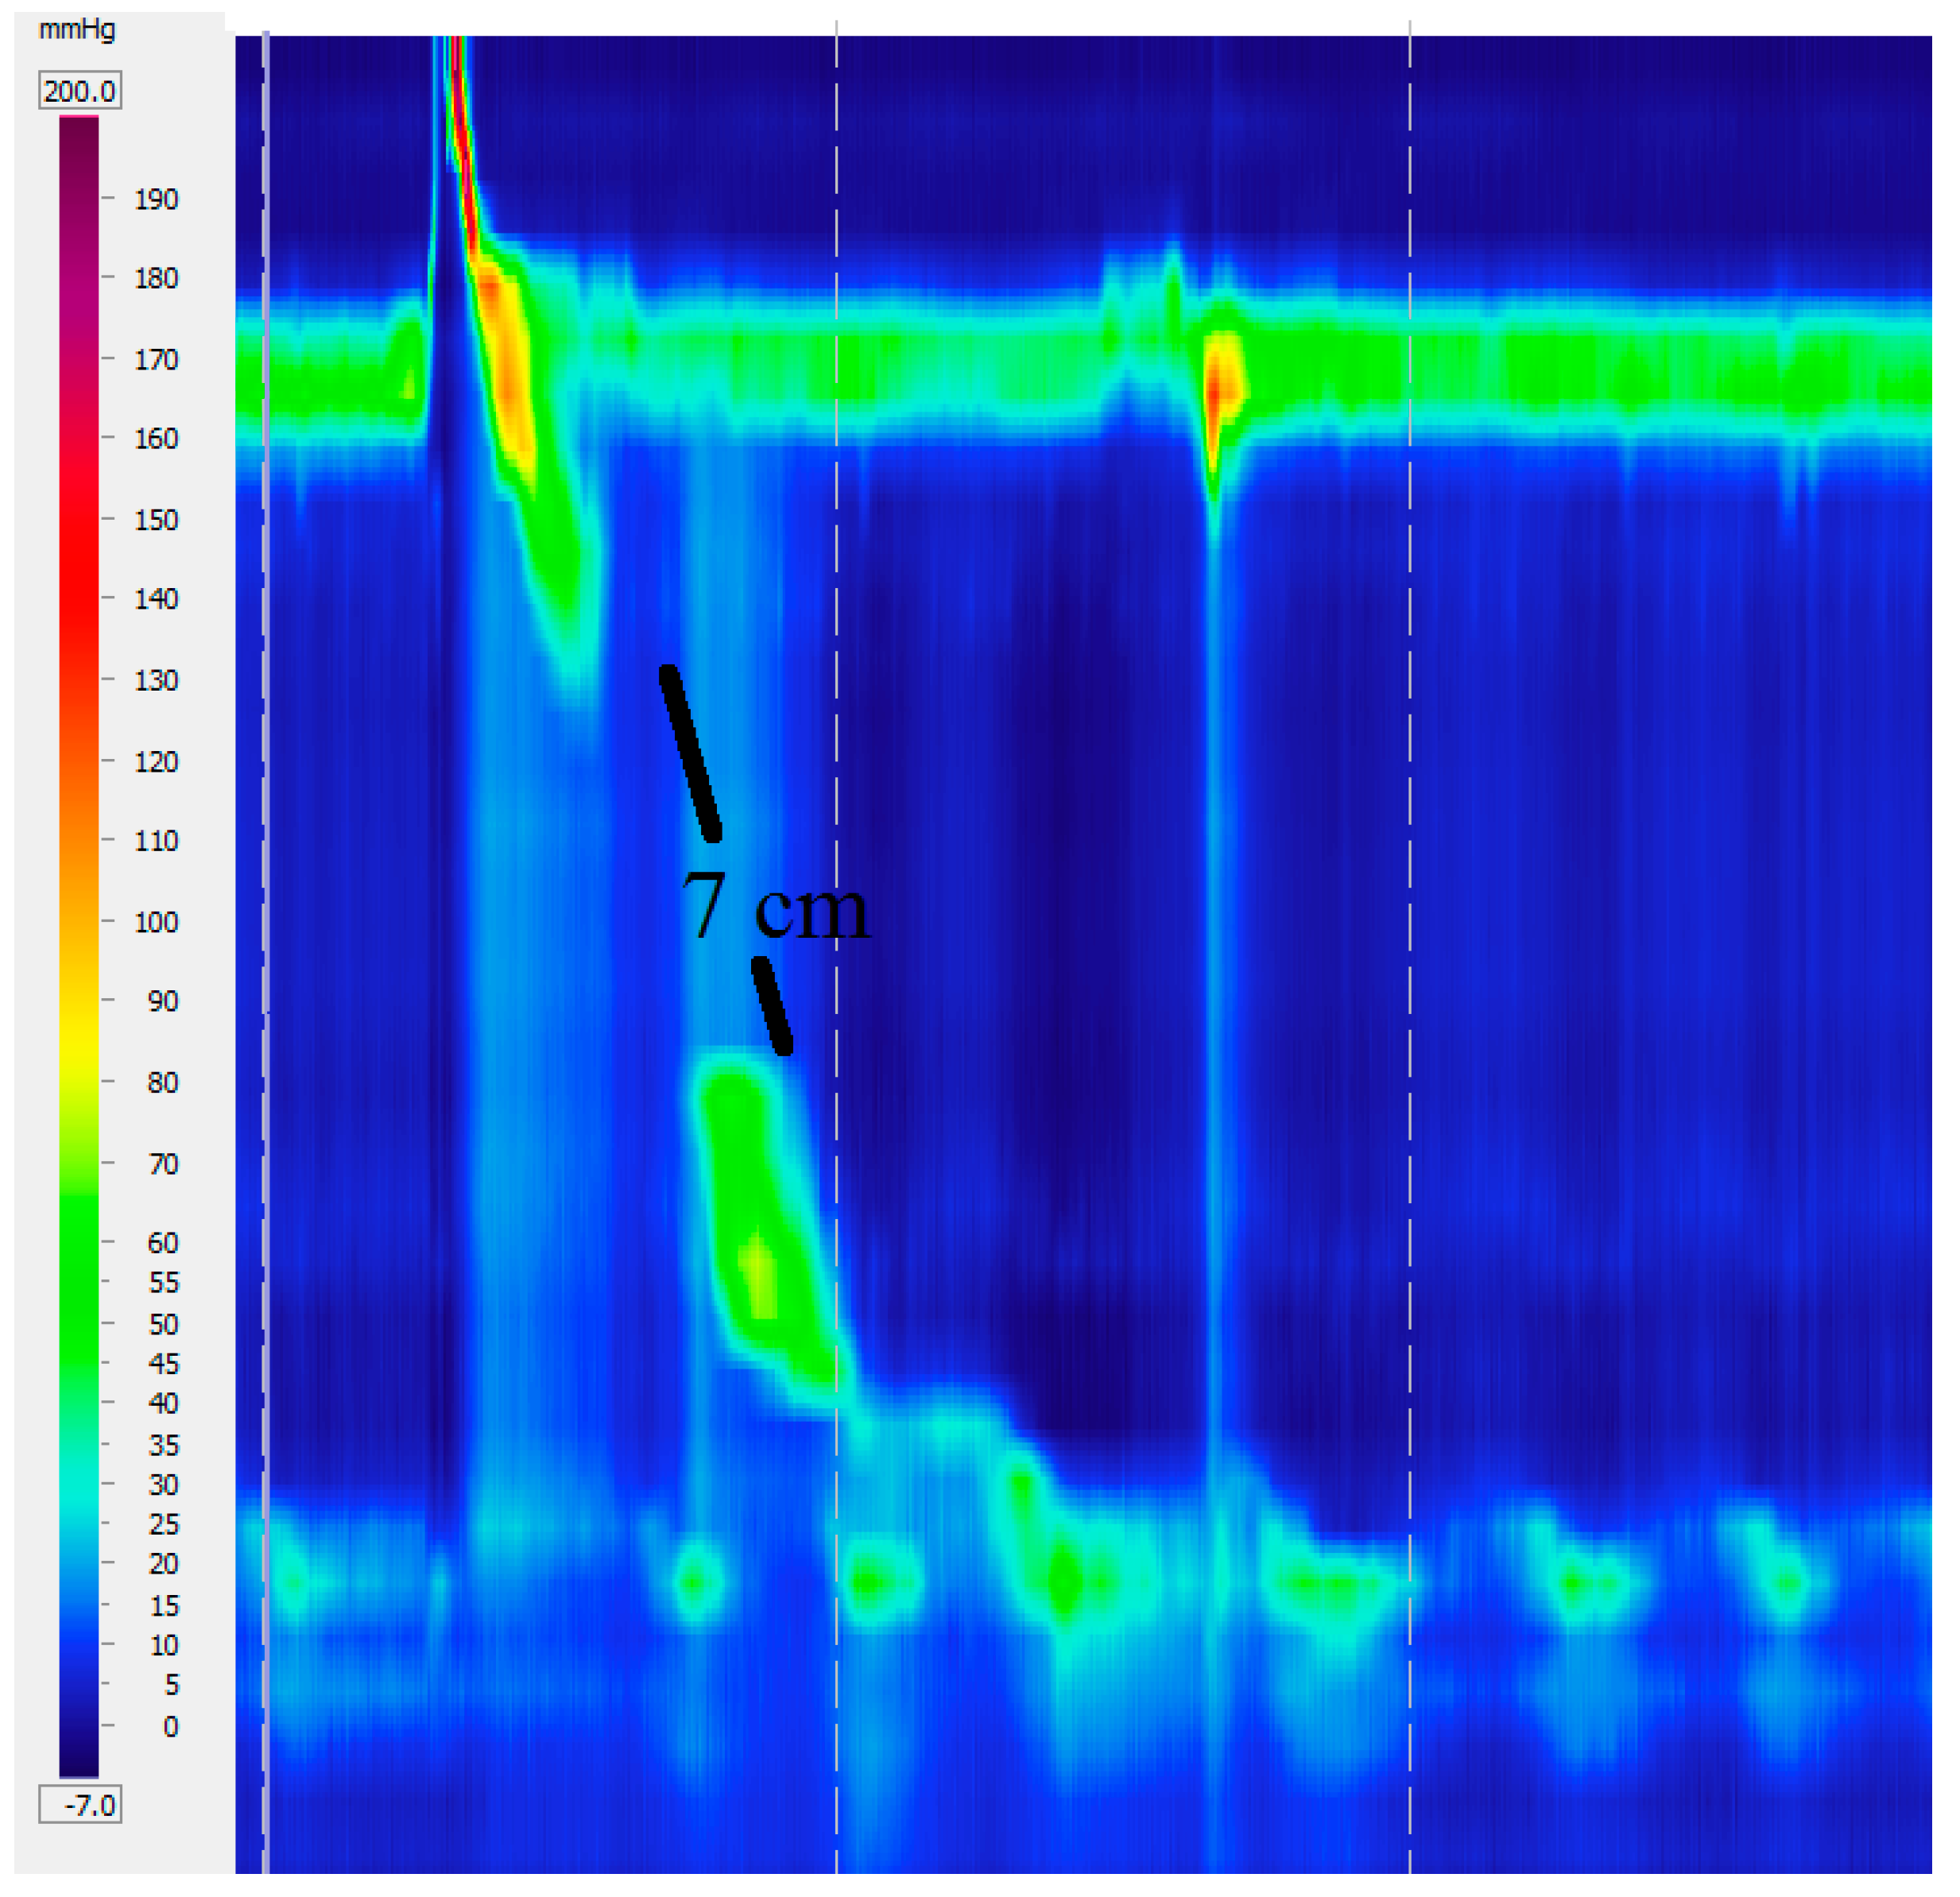

Fragmented peristalsis is defined by ≥50% fragmented contractions with normal contraction vigor (Figure 5).

Figure 5.

Fragmented peristalsis with a 7 cm gap.

The concept of fragmented peristalsis changed radically from previous versions to the version 3.0. Only large breaks (>5 cm) with normal peristalsis are included. This is more clinically relevant, since incomplete bolus transit is observed in 100% of the cases of large breaks but only in 16% of small breaks [19]. It is unclear how to treat this finding since there are no studies focusing on the treatment for this disease under these criteria. There are no studies evaluating changes in the motility pattern after therapy for gastroesophageal reflux disease as well, since both conditions are frequently associated.